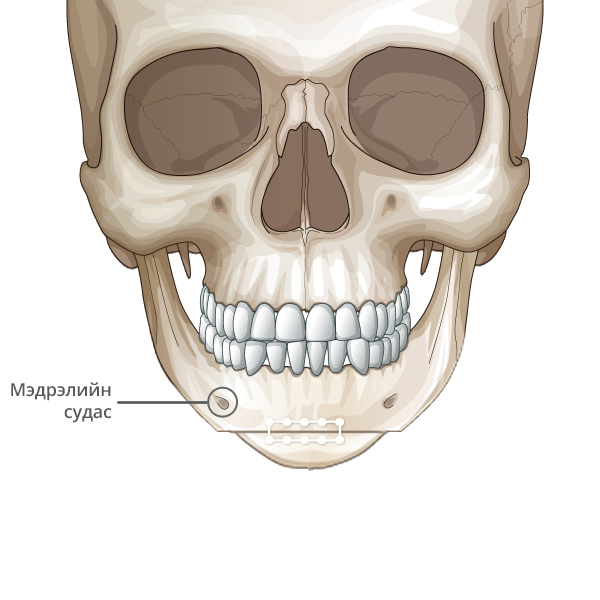

Мэдрэлийн судаснаас зайлсхийж, эрүүний төгсгөлд зүсэлт хийнэ.

Ясны гол хэсгээс тайралт хийж авна.

Зүсэлт хийгдсэн эрүүний хоёр талыг нийлүүлнэ.

Эрүүний ясыг нийлүүлж тогтоож өгнө.